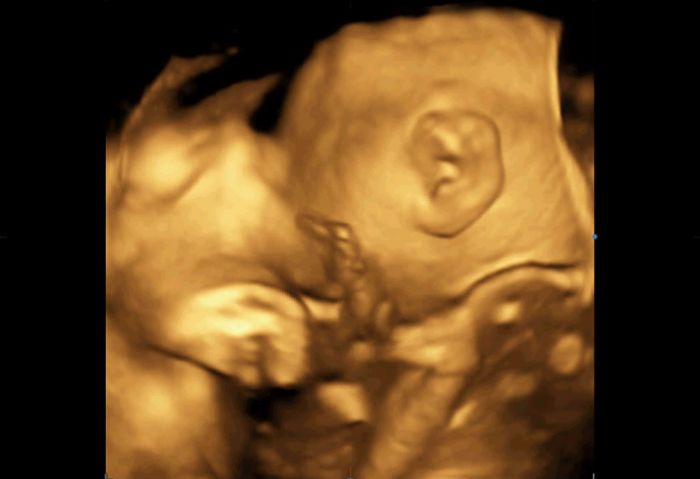

No a minulou středu 3D/4D u mého obvodního gynekologa ( má opravdu dobře vybavenou ordinaci). Nejdřív jsem si myslela, že se nám to moc nepovedlo, páč se nám většinu času schovával za ručičku, ale dle toho, co slyším od ostatních to vlastně byl úspěch

Přikládám fotečky uložené z videa na DVD , které nám dal dr.